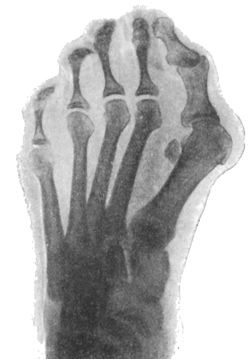

295 157.Radiogram of Hallux Valgus

296 158.Radiogram of Hallux Varus or Pigeon-Toe